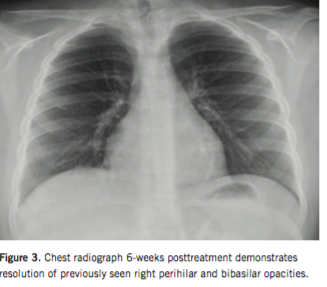

Corticosteroid treatment was initiated with subsequent transition to immunomodulator maintenance therapy. The boy responded rapidly to induction therapy. Granulomatous pulmonary involvement resolved 6 weeks into therapy (Figure 3). At 2-year follow-up, the boy continued to have a sustained clinical and biochemical remission.